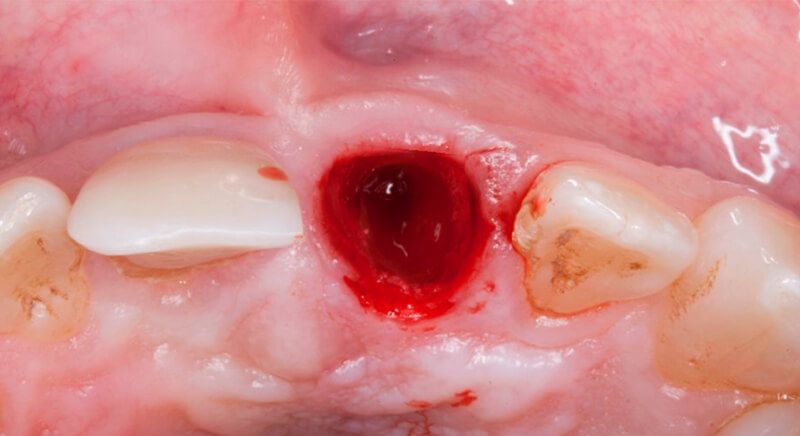

It was decided to reconstruct tooth 1.1 and perform endodontic work up to the fracture line of tooth 2.1 so it could be maintained provisionally, but the patient was very uncomfortable and unable to chew in this area so it was finally decided to extract both the coronal part and the fractured apex of tooth 2.1.

Once tooth 2.1 had been extracted, it was decided that it was not advisable to place an implant immediately as the bone conditions were not ideal and the gum did not have sufficient thickness. We opted for a treatment to preserve the socket and to delay implant insertion.

The socket was filled with a xenograft after the extraction and a graft of connective tissue was placed in the vestibular area of the two upper central incisors.